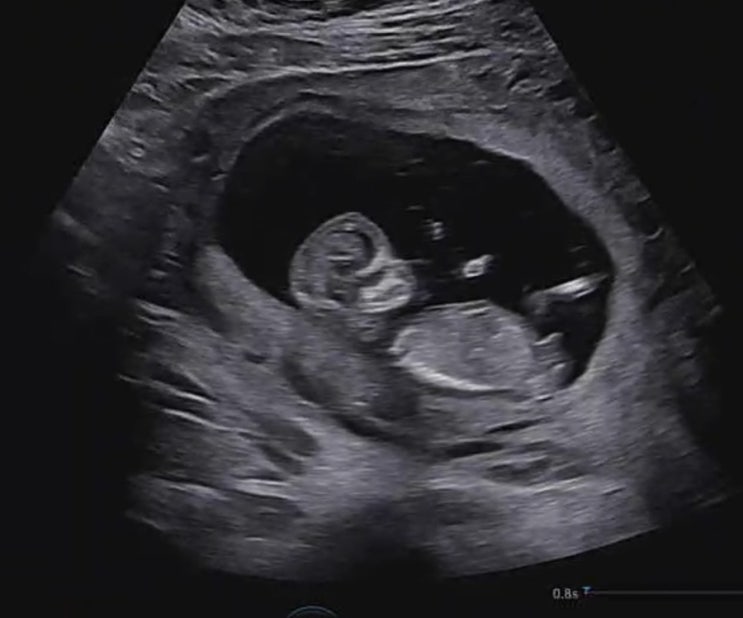

??? 임신17주 - 20주 / 임신 중기 진입 이것이 안정기의 행복?

??? 임신 14주 - 16주 / 안정기 돌입 / 운동시작 / 2차 기형아검사 / 성별확정 ?️ / 양막밴드

??? 임신 11주 - 13주차 / 입체초음파, 1차 기형아검사, 나의 생일주간 !

??? 임신 4주 - 10주차 / 안또용의등장 , 또 어 반 (또용아 어서와 반가워)